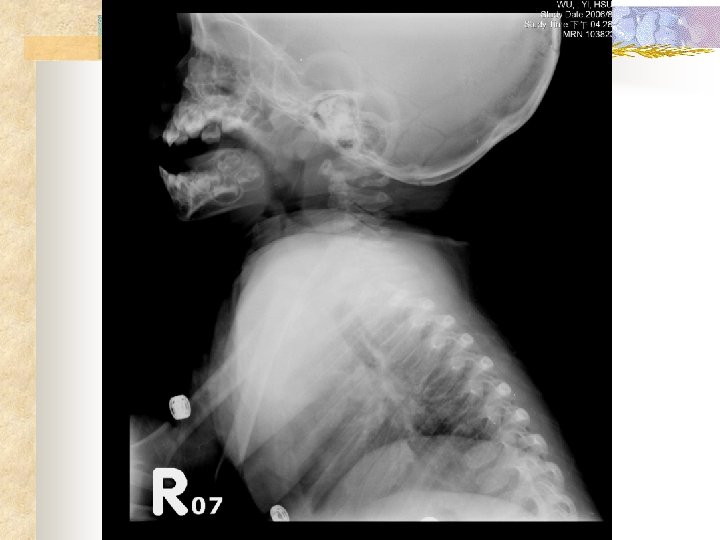

Initial order (11 min) n n Dexamethasone 1 PC IM stat, Bosmin 1 PC inhalation stat CXR, C-spine extension lateral view

Stridor assessment Neck radiographs: n Retropharyngeal abscesses a retropharyngeal space greater than 7 mm anterior to the inferior border of the second cervical vertebral body, or a retrotracheal space greater than 14 mm in children anterior to the inferior border of the sixth cervical vertebral body

Stridor assessment Neck radiographs: n Croup AP view steeple sign subglottic arch becomes edematous n Croup lateral view distended hypopharynx and subglottic haziness

Stridor assessment Neck radiographs: n epiglottitis lateral view an edematous epiglottis with the thumb sign, enlarged aryepiglottic folds, and a ballooned hypopharyngeal airway n 70 percent of all patients with epiglottitis have radiographic findings interpreted as normal